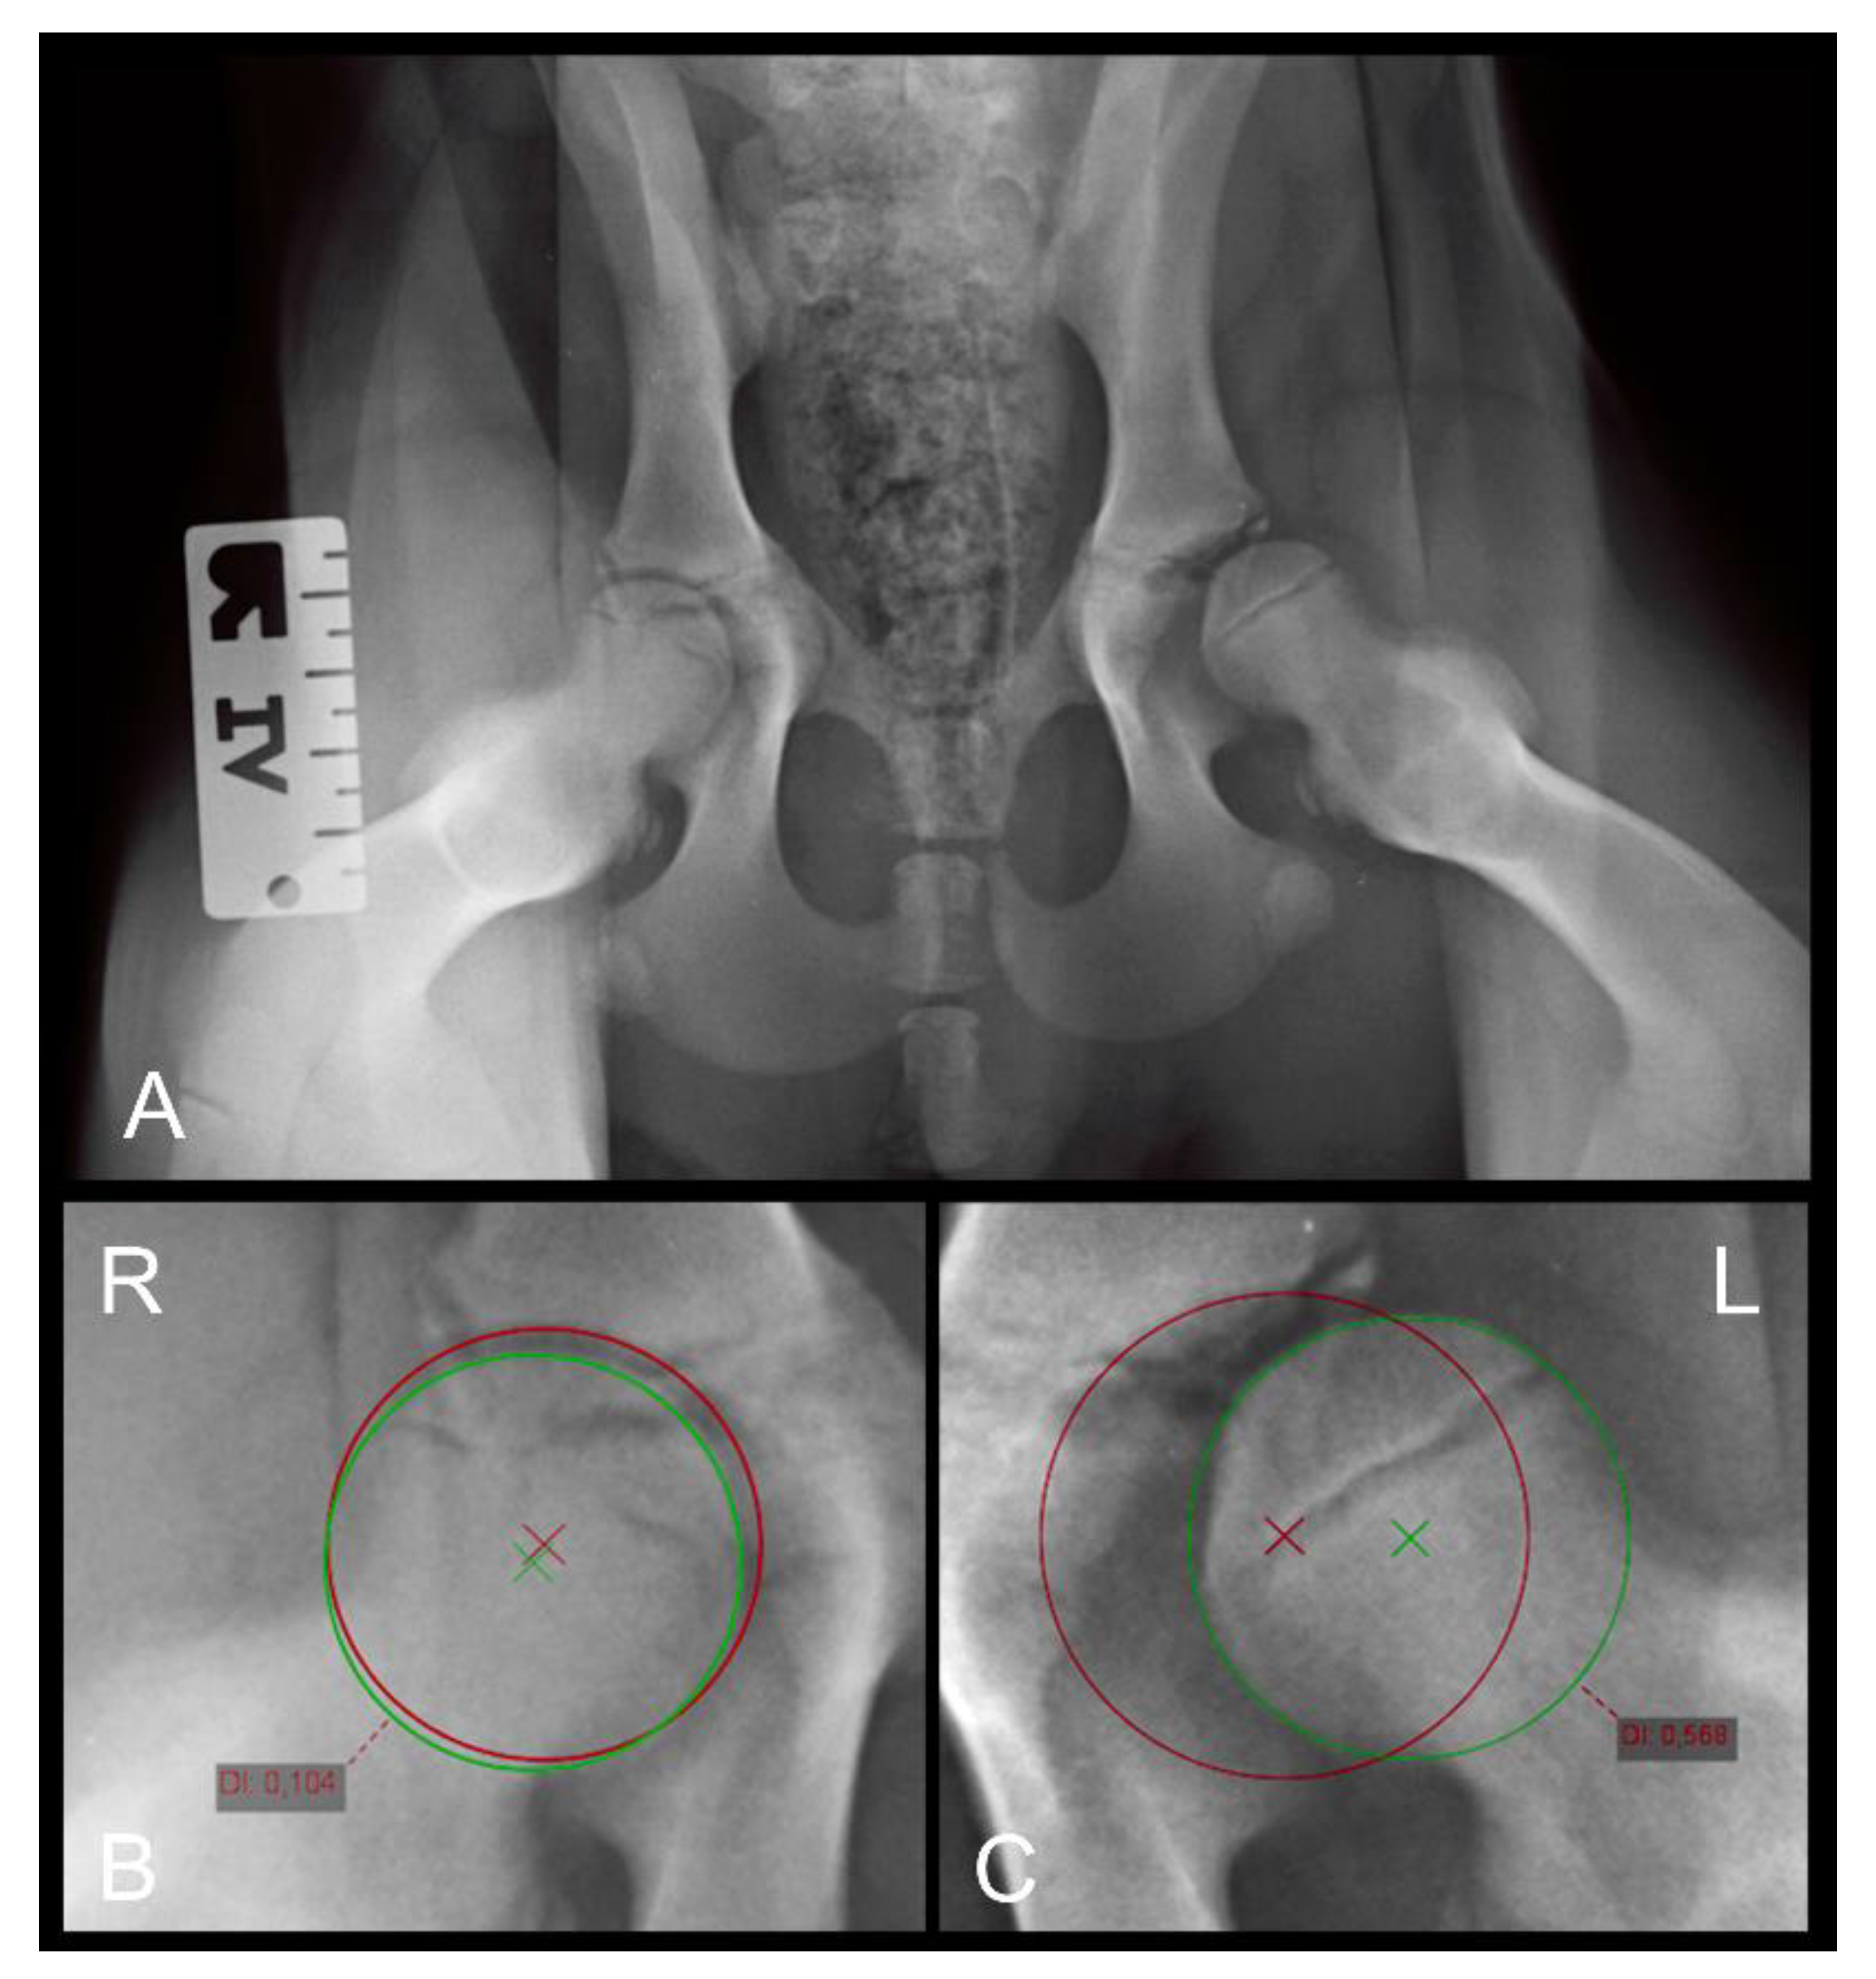

2.5.5. The Distraction Index (DI)

To quantify the DI, ventrodorsal distraction view radiographs (Badertscher method modified by Vezzoni) were taken, and the calculation of the DI was performed using the PennHIP measurement method [26]. The DI is calculated by dividing the distance between the centers of the femoral head and acetabulum by the radius of the femoral head during distraction and is a number between zero (healthy hip) and one (severe laxity). The incidence of hip laxity in dogs with DI ≤ 0.3 and DI ≥ 0.6 is reported to be low and high, respectively [34]. The measurement of the DI on the distraction view radiograph is shown in Figure 2.

Figure 2. (A) Distraction view VD radiograph of a four-month-old Rottweiler (same dog as in Figure 1A,B). (B) A magnification of the right and (C) a magnification of the left hip joint demonstrating the distraction index measurements. Note the laxity in the left joint which was not obvious in the extended view.